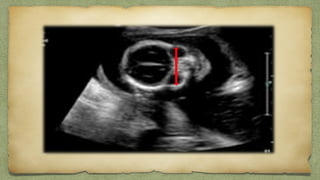

VENTRICULOMEGALY

Ventricular size measurementsโ€ฆ

1.Atrial width

Atrial Width

๏ฑ Most useful and accepted

๏ฑ Must be taken on true axial view

๏ฑ Measured at widest part of ventricles

๏ฑ Inner to inner vent walls

10-12 borderline

12-15 moderate

>15 severe